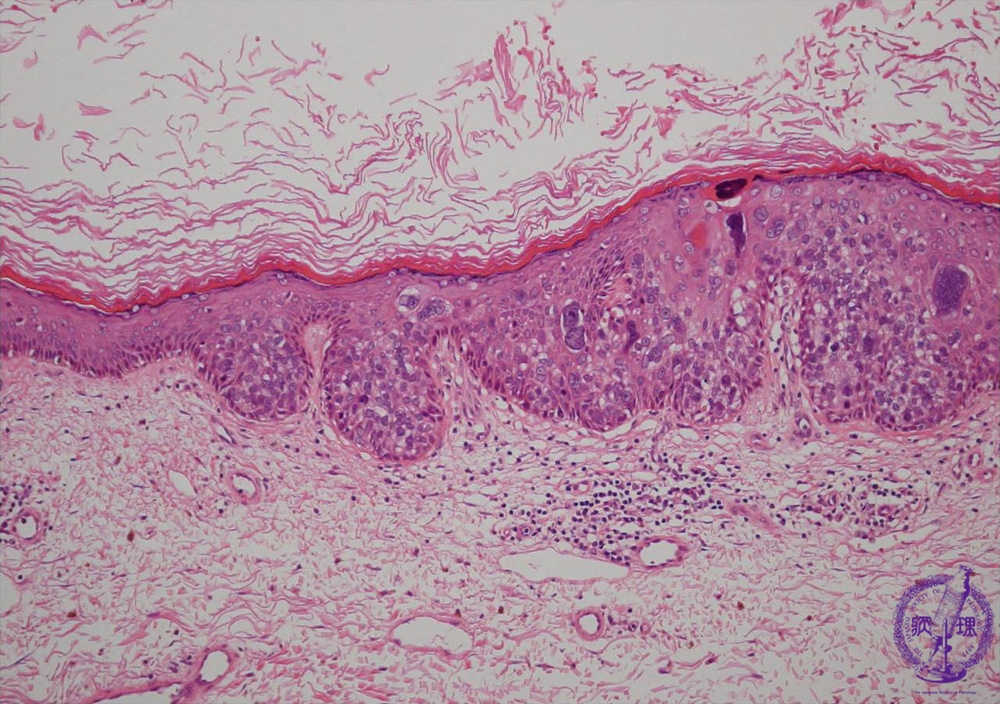

- ★(8)Squamous cell carcinoma(Bowen disease)

Microscopic findings: Bowen’s disease is one of the intraepidermal squamous cell carcinoma. It sometimes occurs with other internal malignancies.